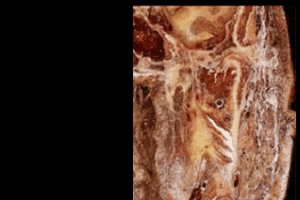

En este contexto, el Diplomado en Anatomía de Cabeza y Cuello ofrece una oportunidad única para profundizar en el conocimiento de las regiones craneales y cervicales. Este diplomado, que tiene una duración total de dos semestres, aborda el estudio de la cabeza en un semestre a través de dos capítulos que permiten su análisis detallado. De manera similar, el cuello se estudia en dos capítulos, incluyendo nociones básicas de tórax y mediastino superior, lo que brinda un contexto más amplio a los contenidos.

El aprendizaje se desarrolla mediante una metodología innovadora que combina talleres de reconocimiento de estructuras, disección en cadáveres humanos, estudio autodirigido, clases expositivas a través de Zoom y evaluaciones realizadas en la plataforma LMS (Moodle) de educación continua

Dirigido a profesionales de la salud y docentes de ciencias anatómicas, este diplomado permite a los participantes adquirir conocimientos teóricos y prácticos. Los estudiantes se formarán mediante sesiones prácticas en el pabellón de anatomía, disección de cadáveres, clases de anatomía y aplicación clínica de los contenidos abordados. Estos recursos teórico-prácticos aseguran un conocimiento profundo de la anatomía y la morfología de la cabeza y el cuello, combinando excelencia académica y aplicabilidad clínica.